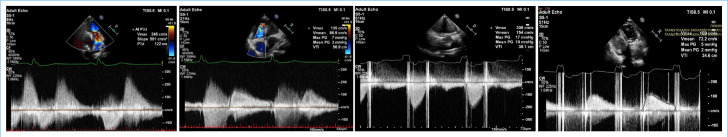

Surgical treatment is recommended in patients with symptomatic severe tricuspid regurgitation and pulmonary regurgitation. Although renal transplant patients are a high-risk patient group for cardiac surgery, heart valve surgeries can be performed successfully. There are a limited number of studies published on this subject in the literature. Therefore, we present a case who underwent tricuspid ring annuloplasty (TRA) before being followed up with renal transplantation and then successfully performed redo tricuspid valve replacement (TVR) and pulmonary valve replacement (PVR).